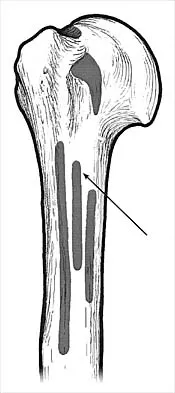

What muscle attaches to the site shown by the arrow in Figure 2?

The latissimus dorsi inserts on the humerus metaphysis between the pectoralis major (posterior) and teres major (anterior). Teres minor inserts on the base of the greater tuberosity. Pectoralis minor does not insert on the humerus. Williams PL, Warwick R, Dyson M, Bannister LH: Neurology, in Gray's Anatomy, ed 37. Edinburgh, Scotland, Churchill Livingstone, 1989, pp 1131-1132.